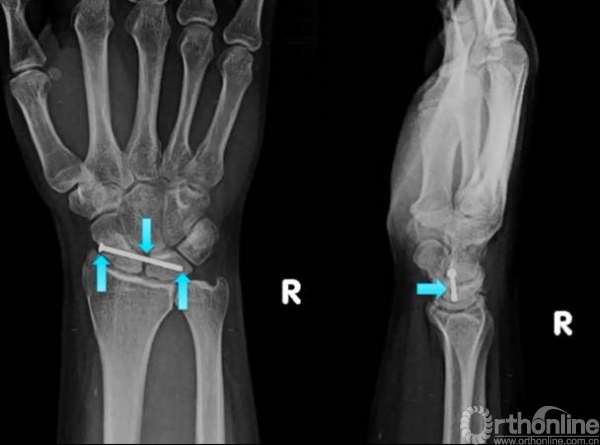

透视可见两枚复位克氏针和一枚固定的螺钉,固定螺钉一般采用三层皮质固定舟月微动关节。

术后可见舟月关节恢复。